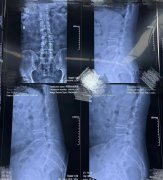

患者男,67岁,10年来腰痛缠身,休息后缓解,劳累后加重。近1年来腰部及右下肢疼痛、麻木不适。随着患者腰痛逐渐加重,经多方了解,家人陪同找到陕西冶金医院神经脊柱科就诊。入院后完善检查诊断为腰椎间盘突出、腰椎管狭窄。

▲术前X片

经过周密细致地术前讨论及评估,由张少华主任主刀,熊东医生、手术室(麻醉科)默契配合,为李先生成功实施“OLIF腰椎微创椎体间融合术”,目的:减压,复位,融合;术中操作干净利落、精准微创,顺利完成,手术历时近4小时。